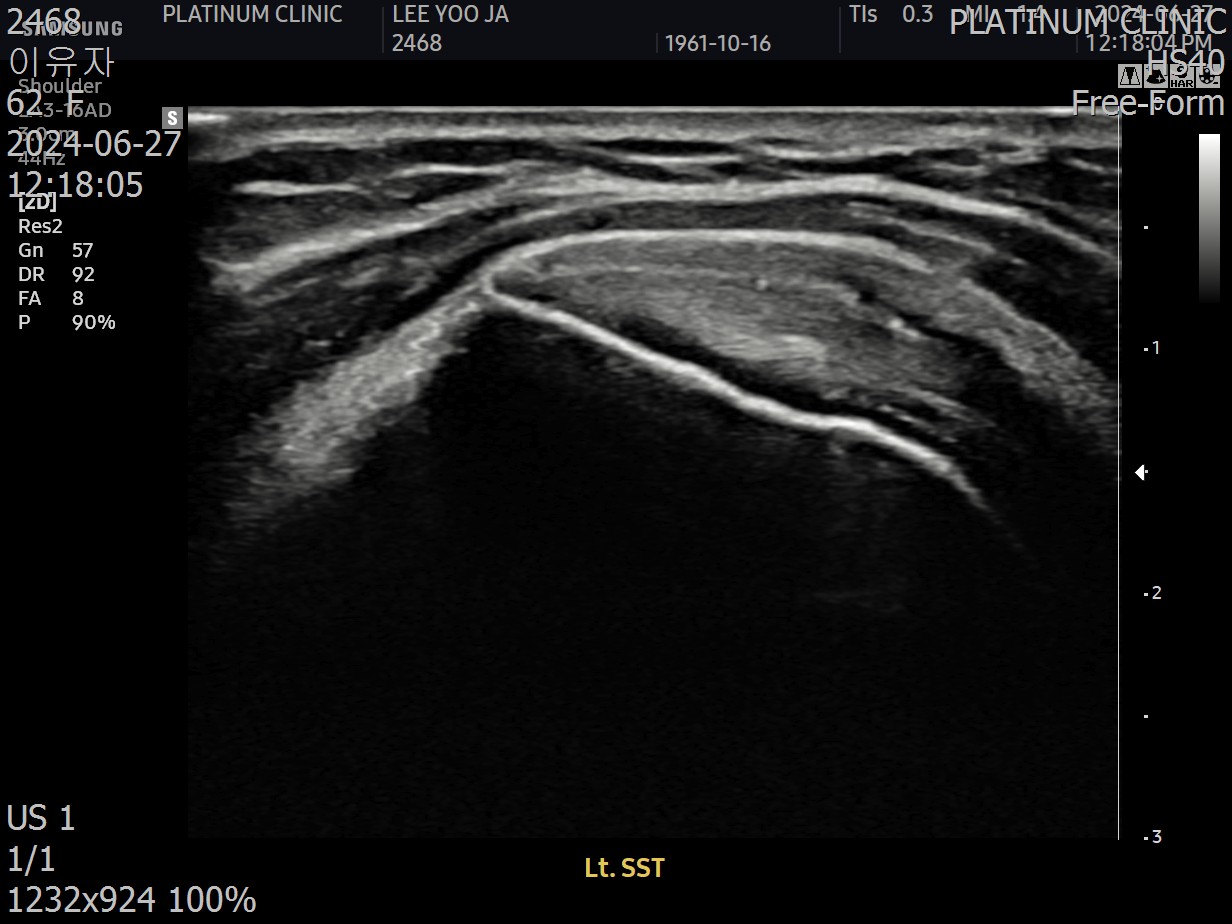

저는 이학적검사를 시행한 뒤, 초음파 검사를 진행했습니다. 그리고 발견했습니다.

회전근개 힘줄 사이사이에 미세한 석회 침착이 여러 군데 흩어져 있었습니다. 크기가 매우 작아서 3mm 단위로 단면을 촬영하는 MRI에서는 보이지 않았지만, 초음파로는 선명하게 확인되었습니다.

진짜 원인은 오십견이 아니라, 오십견을 유발하는 '석회'였습니다.

근본 원인인 석회를 제거했습니다. 초음파로 확인된 미세석회들을, 석회분쇄흡입술을 통해 힘줄 사이사이에서 씻어내듯 제거했습니다.

초음파 검사에서도 석회는 깨끗이 사라졌고, 관절낭 유착도 재발하지 않았습니다.